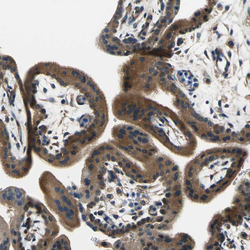

- Experimental details

- Immunohistochemical staining of human placenta shows moderate cytoplasmic positivity in trophoblastic cells.

- Sample type

- HUMAN